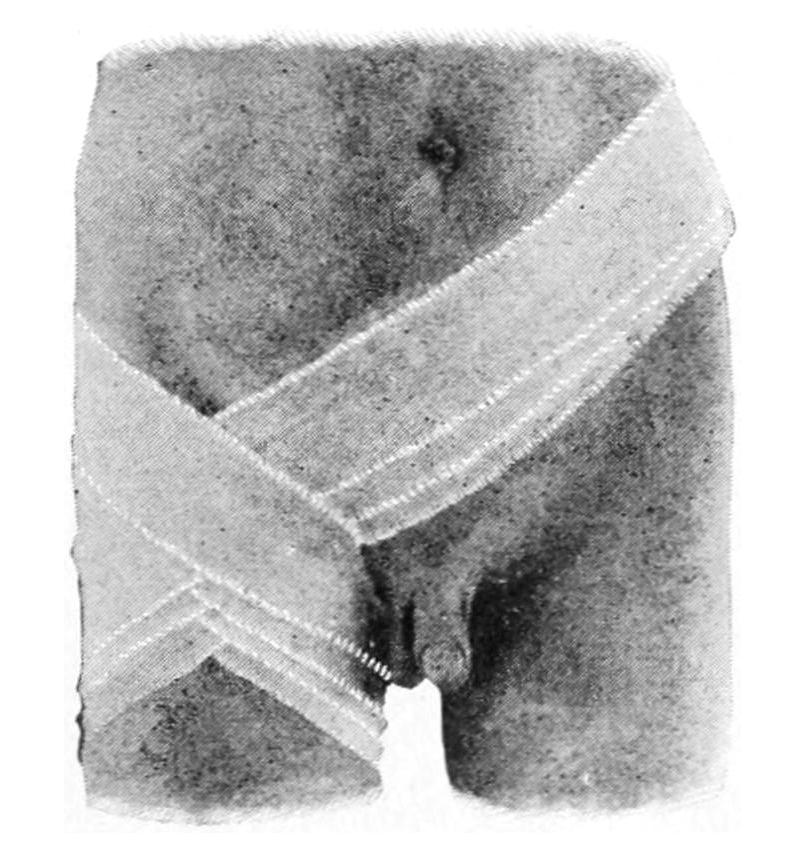

The total amount of blood in the human body has been variously estimated at from one-eleventh to one-twenty-fifth of the body weight, the average being about one-sixteenth. The amount which the body may lose and still retain vitality is very vague and differs not only with individuals, but very greatly under various conditions. Severe loss of blood is one to be atoned for as quickly as possible, and is to be prevented as far as it can be after accidents or during operation. For this reason the so-called bloodless method of operating upon limbs, by the use of the rubber bandage, constituted a great advance in surgery. For the same reason the use of hemostatic forceps is of equal value in operating upon other parts of the body; other things being equal the quickest and most satisfactory recoveries follow the bloodless operations, and it is an advantage to conserve this vital fluid as far as possible.